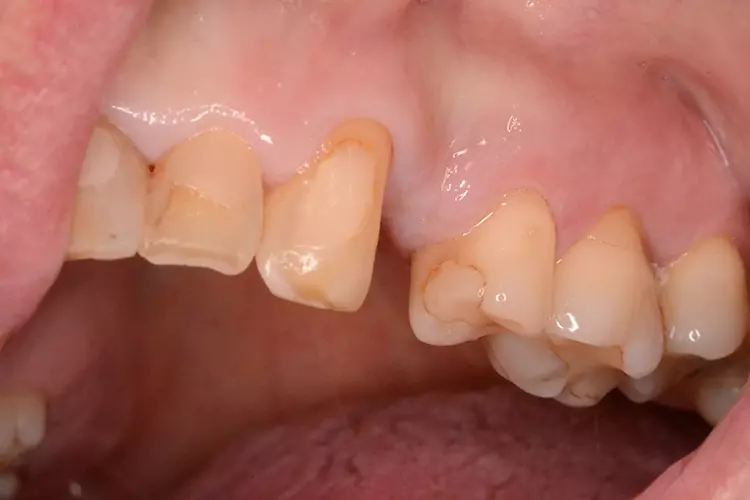

Neugestaltung der Front bei starken Zahnfehlstellungen

Bei dem heute 49-jährigen Patienten wurde seit Kindertagen versäumt, die Ober- und Unterkieferzahnbögen kieferorthopädisch auszurichten. Der Patient leidet seitdem stark unter seinen Zahnfehlstellungen.

Die Fraktur des stark elongierten Zahnes 21 war für den Patienten der Ausgangspunkt, sowohl die Front des Ober- als auch des Unterkiefers prothetisch überarbeiten zu lassen. Dabei wurde der frakturierte Zahn 21 durch ein navigiert eingesetztes Sofortimplantat ersetzt, während die verschachtelt stehenden Zähne 12 und 42 durch eine Brückenversorgung korrigiert wurden (Abb. 4a-j).